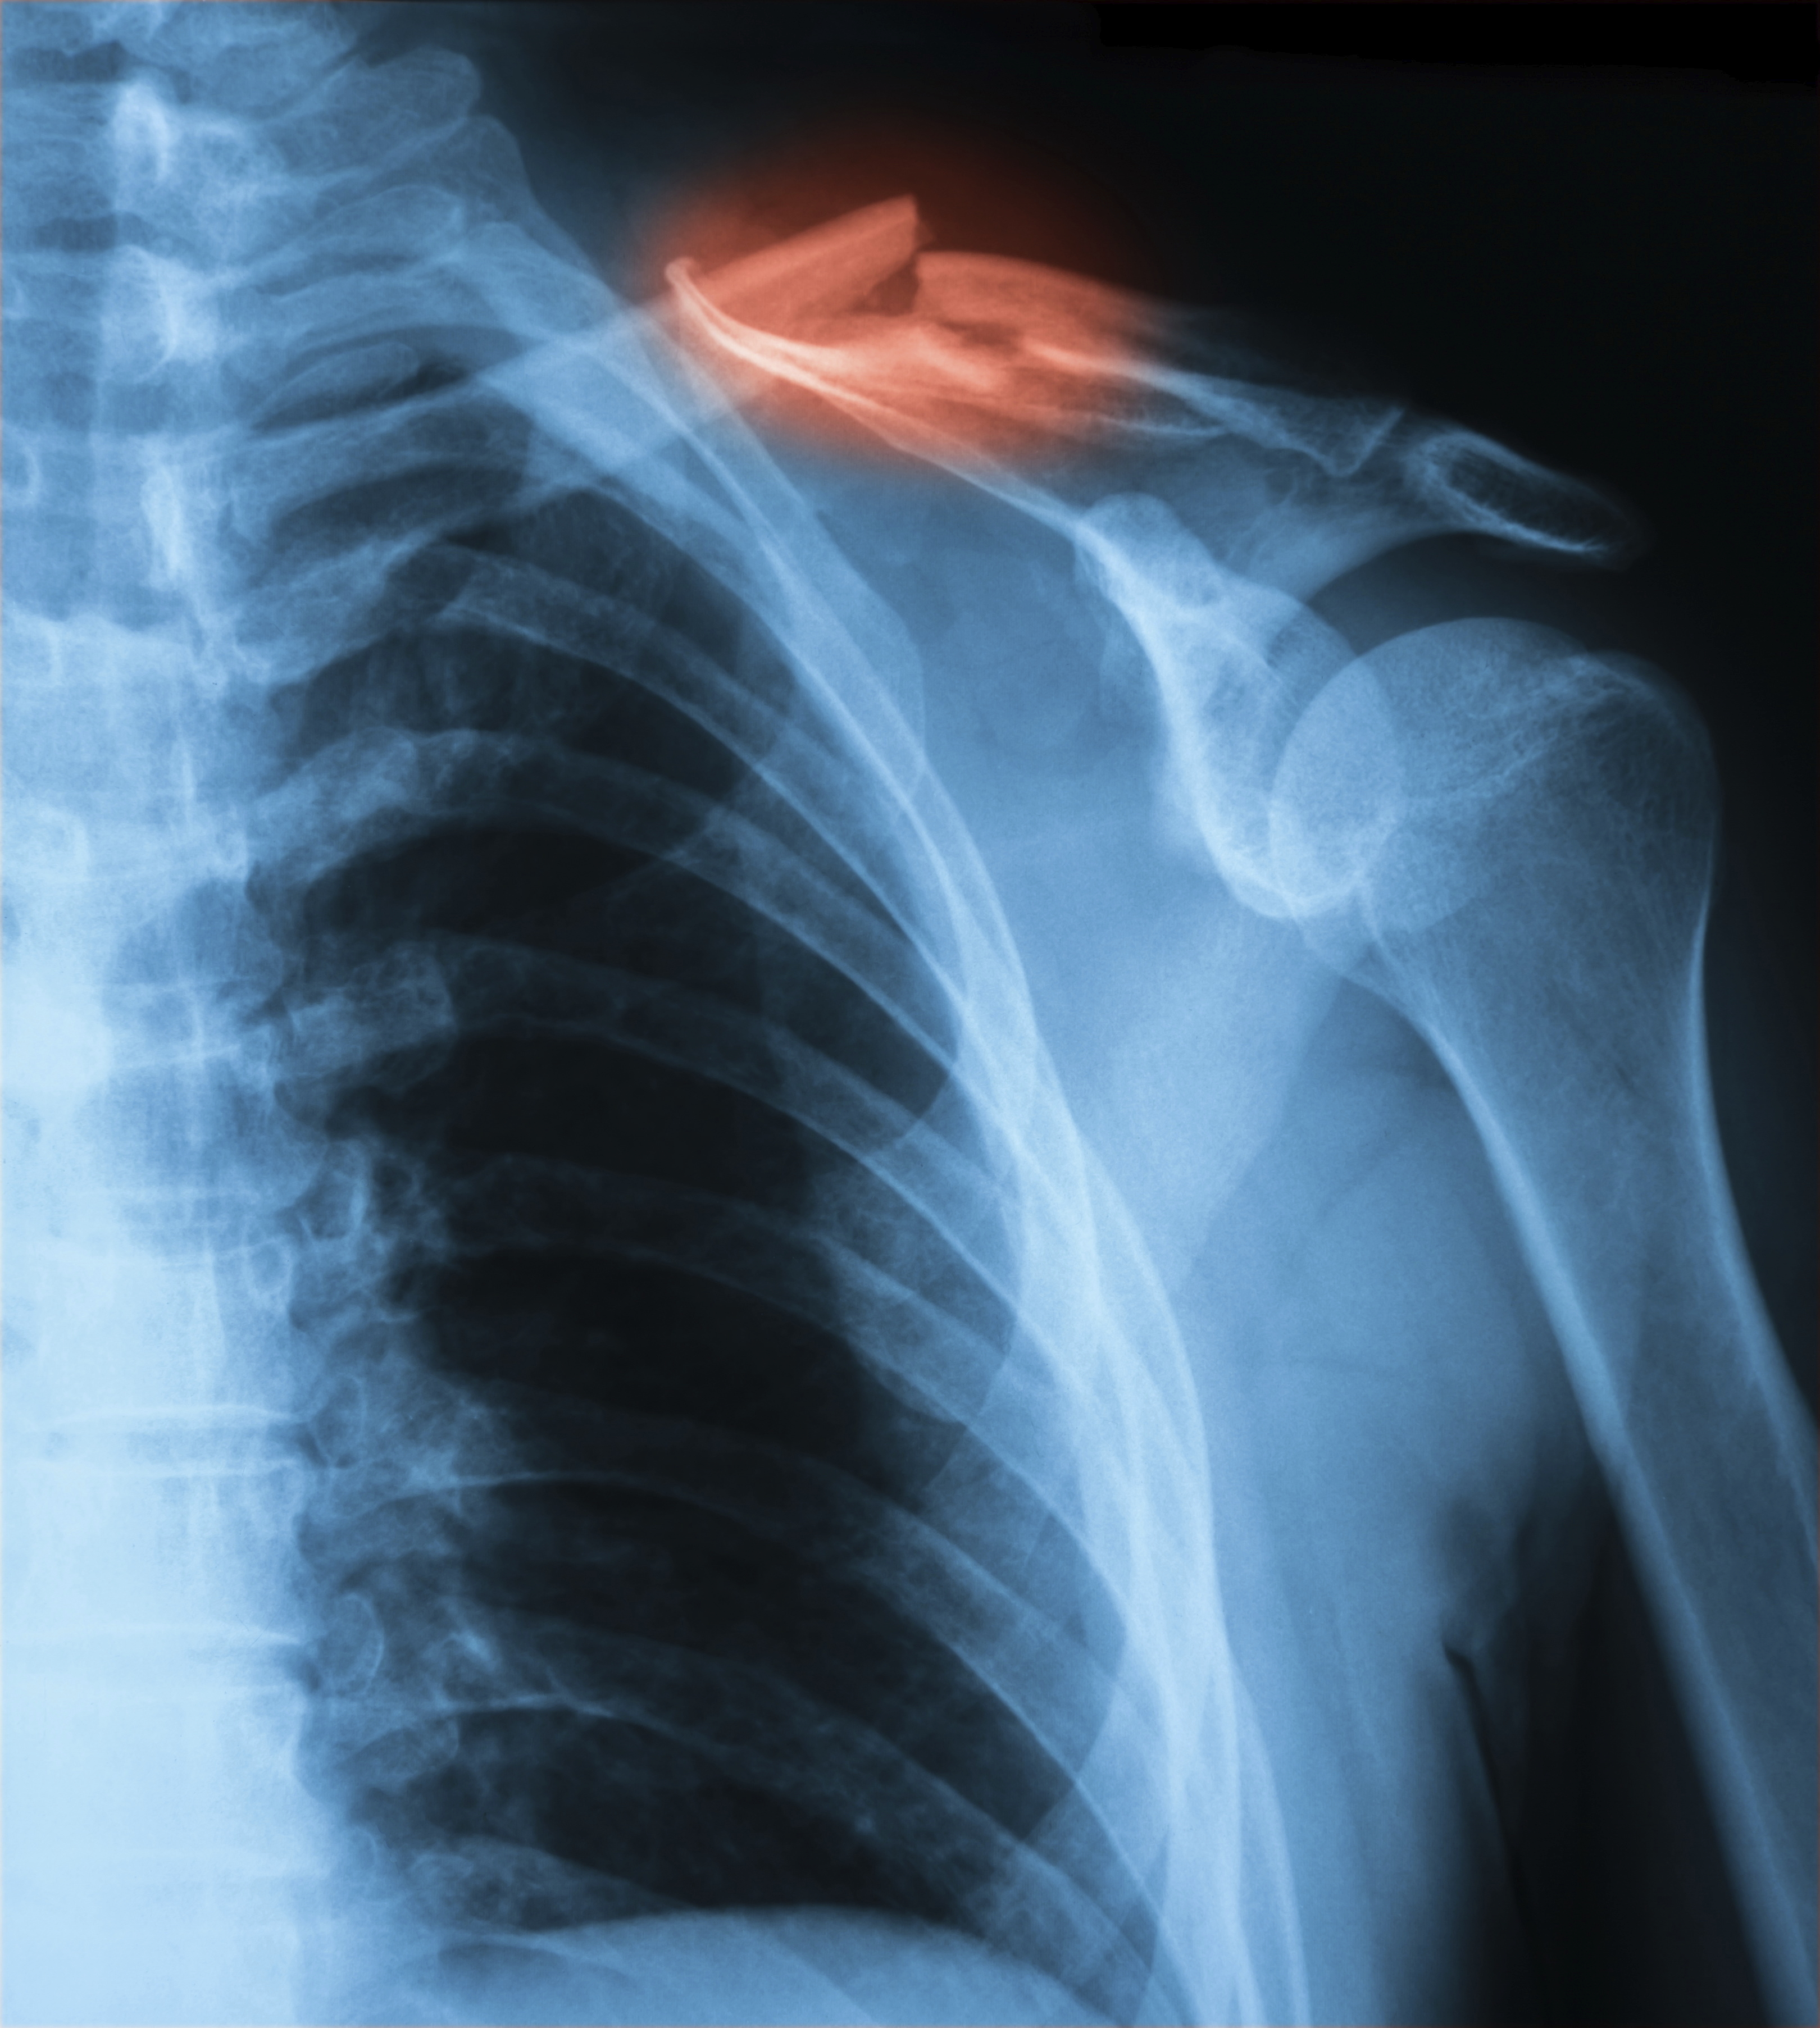

Each of these conditions may vary in severity and thus may require different types of medical or rehabilitative treatments. In extreme cases a clavicle fracture may also be present due to the traumatic nature of the injury. This particular condition must be ruled out with radiographic testing to ensure each injury is properly managed and that each player returns to play as safe and as fast as possible. In extreme cases surgery is required to maintain the individual’s overall structure of their clavicle and long-term function of the shoulder.

The radiographs below are of a 39 year old male that collided into the boards with an out stretched arm fracturing his clavicle into 4 pieces. After his surgical intervention and physical therapy program he returned to the ice with no physical restrictions or limitations.